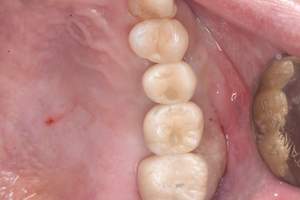

症例写真-2

- Befor

- 途中経過

- After

| 年齢 | 50代・男性 |

|---|---|

| 主訴 | 右下歯が疼く |

| 治療内容 | ・右下6番インプラント ※1:FGG(遊離歯肉移植術)とは、足りない歯ぐきを上顎から上皮を切り取り移植する外科手術 |

| 治療費 | 合計:902,000円(税込) ■内訳 |

| 治療期間 | 9ヵ月 |

| 治療方針 | 右下の当該歯は歯根破折により保存不可能と診断しました。歯周疾患も伴っていたため抜歯後に骨吸収※1が大きく起こることが予測できました。チタンメッシュ併用骨再生誘導法(GBR※2)を選択しインプラント埋入と同時に行い自然な歯槽骨のラインを再現しました。またGBRを行う際にインプラント辺縁の付着歯肉の減少が起こる為、遊離歯肉移植術(FGG※3)を行い清掃性を考慮した形態に仕上げました。 ■治療方針の解説 治療した右下の歯をレントゲンで撮影したところ根本の部分に黒く写る箇所があり「根尖性慢性周囲炎※1」と診断。また歯周病も進行していました。 ※1 骨吸収・・・歯槽骨という歯を支える骨がなくなっていくこと |

| 担当者所見 | 主訴の右下だけでなく歯茎の腫れ、発赤があり不良補綴や不良充填など他にも治療箇所が多数ありました。プラークコントロールが不良であった為まずはブラッシング指導を行いセルフケアの重要性を理解していただくところからスタートしました。 右下6番の歯はインプラント治療を行なった結果審美的にも機能的にも患者様の満足を得ることができました。骨造成と歯肉移植も行なった為インプラントを支える十分な歯周組織の獲得ができたと思っております。 |